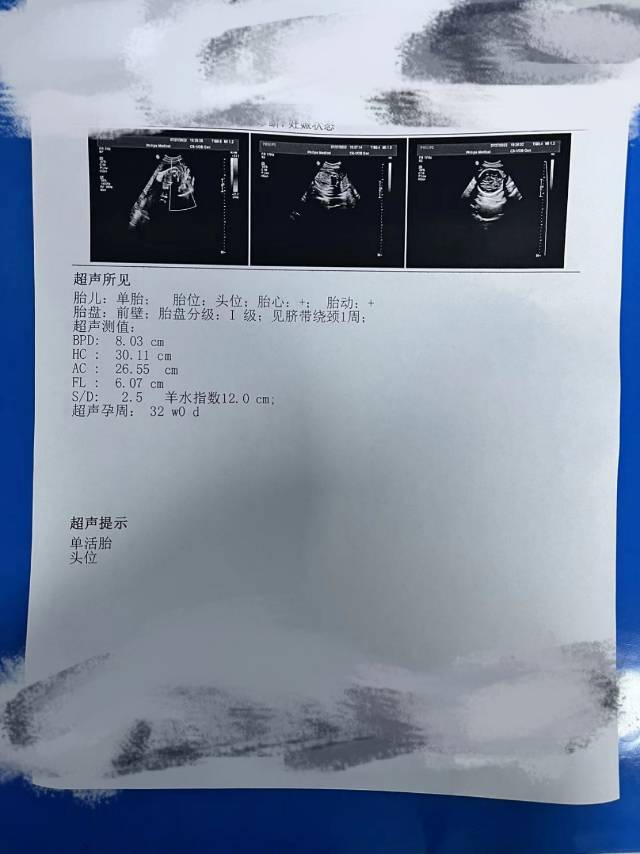

大夫这个腿可以吧,没事吧,不短吧,担心死了